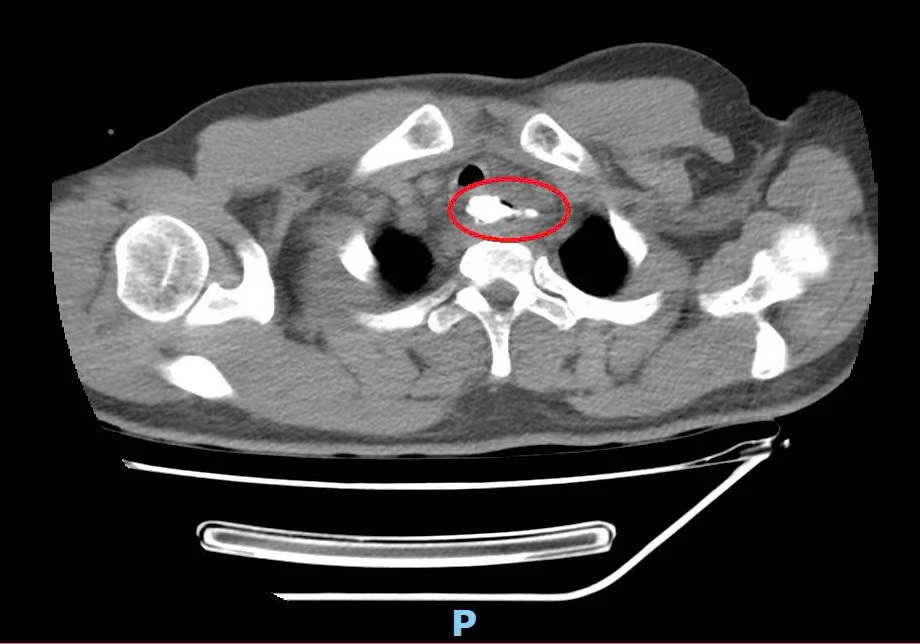

Qua thăm khám và kiểm tra, các bác sĩ phát hiện một dị vật là mẩu xương lớn nằm ở thực quản đoạn ngực, có khả năng gây thủng thực quản, tổn thương nghiêm trọng đến các cơ quan xung quanh.

Dị vật là mẩu xương heo có mấu nhọn, kích thước 30 x 41mm, nằm ở thực quản đoạn ngực, cách cung răng trên 20cm.